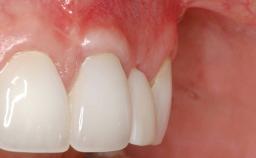

GBR and Soft-Tissue Augmentation Following Explantation to Rehabilitate a Soft- and Hard-Tissue Defect

It is sometimes necessary to remove and replace compromised implants. This case is a clear example of the need for multiple steps to achieve an optimal therapeutic result for patients with non-salvageable implants. It illustrates how the lost soft and hard tissues were rebuilt in a sequence that improved the healing of the hard tissues and assured their long-term stability. The 35-year-old healthy patient presented with clinical attachment loss on the proximal and lingual surfaces of the natural dentition. Some gingival recession was present on natural teeth, particularly in the posterior sextants (S1, S3, S4, and S6).

Soft Tissue Anatomy Intact Defective

Bone Volume Horizontally and vertically sufficient Horizontally deficient Deficient vertically or deficient vertically AND horizontally